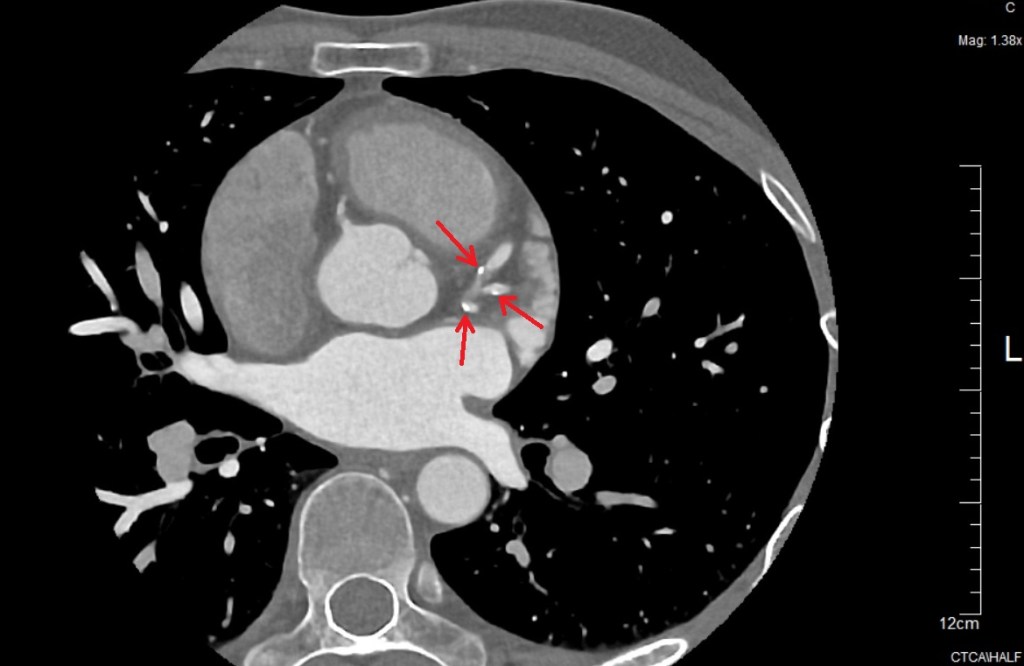

Coronary artery disease starts when cholesterols or other fatty deposits stick on the walls of the arteries in the heart (atherosclerosis). The build-up is generally called plaque. This build-up of plaque can cause the arteries to narrow, blocking blood flow. The plaque can also burst or break away from the wall, leading to a blockage (blood clot in the arteries). It’s serious business. Here’s one image from my CTCA scan:

I have a number of these white “hard” calcium deposits. There is some strong evidence in studies of endurance athletes that long-term endurance training can lead to an elevated level of plaque build-up. These deposits in athletes do tend to be “harder” and more solid, which means that although they can narrow the arteries, they are less likely to break away and cause a total blockage.

While they’re not nothing to worry about, these harder calcium deposits “don’t carry the same meaning in endurance athletes as they do in non-athletes.”